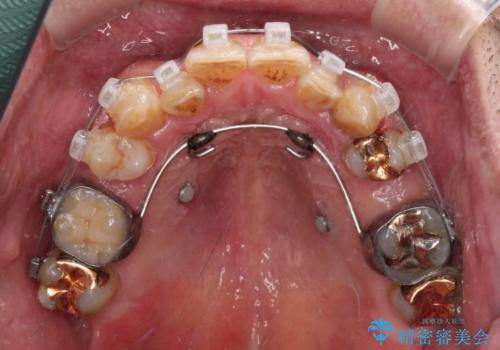

- 矯正装置

- クリアブラケット

奥歯に欠損が多く、矯正治療はやや難航することが予想されますが、患者様の希望もあり、上顎左右小臼歯を1本ずつ抜歯し、ワイヤー装置にて矯正治療を行うこととしました。

矯正歯科治療を行うに当たり、痛みや違和感を感じている歯の根管治療を行い、矯正治療中にインプラント埋入し、補綴治療と矯正治療を同時に終了できるように進めて行くこととしました。